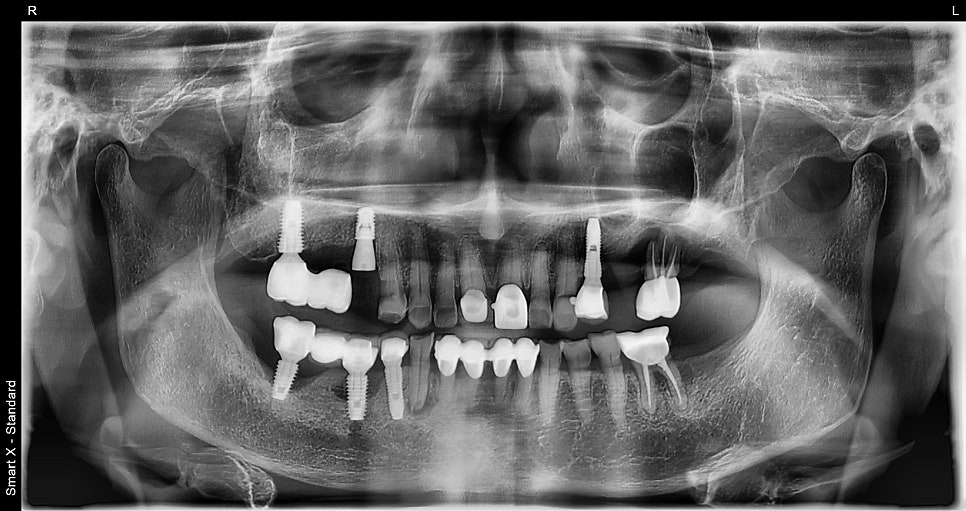

These are the panoramic X-ray and surgical scene immediately after implant surgery.

For #15, where the bone had completely resorbed, an immediate implant was placed after extraction, and the existing #16 implant was removed.

A procedure that is usually performed in two stages (placement and healing abutment connection)

was completed in one visit to reduce the burden of multiple appointments for the patient.